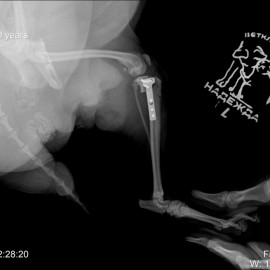

Обратились с жалобами на хромоту на левую тазовую конечность. У собаки отмечается избыточный вес. В клинике был проведен осмотр и рентгенологическое исследование, в ходе которого был поставлен диагноз - разрыв передней крестообразной связки левого коленного сустава. Была проведена операция: TPLO.

Снимок 2 после операции